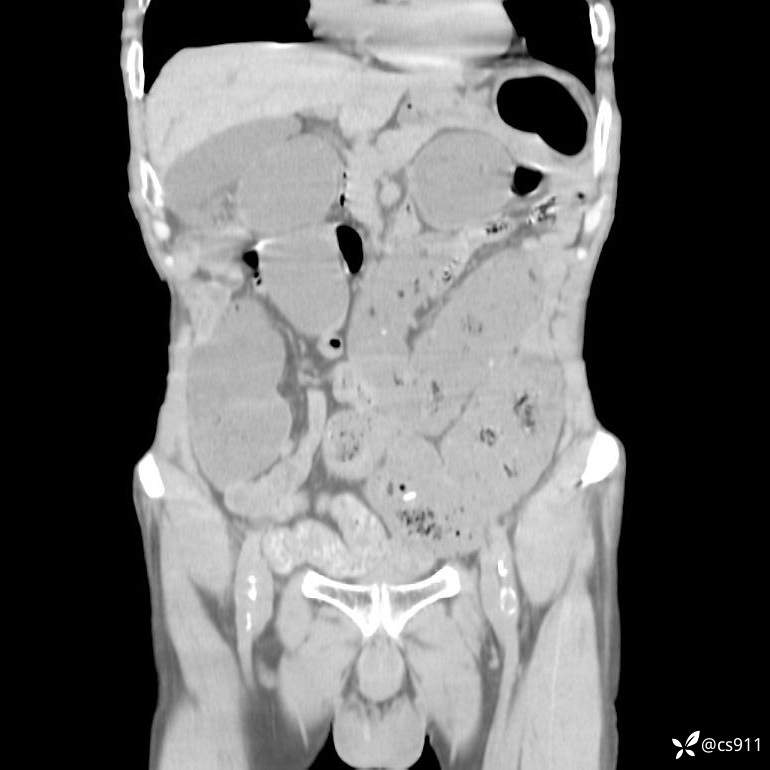

急腹症之急诊CT,原因?答案公布

男,77岁,腹痛、腹胀伴恶心呕吐1天。呕吐胃内容物,非喷射性呕吐,有咖啡色样胃内容物,诉有胃穿孔病史。查体:全腹平,下腹部压痛,全腹无反跳痛,叩诊呈浊音,移动性浊音阴性,肠鸣音减弱,1-2次/分。肛检:直肠未扪及明显肿物,可触及大量粪块。

T 36.6℃ P 80次/分 R 26次/分 BP 100/60mmHg

白细胞(WBC) H 14.55 10e9/L 4-10

中性粒细胞百分率(NEUT%) H 85.7 % 40-75

血淀粉酶(AMY) HH 1859 U/L 35-135

癌胚抗原(CEA) H 27.44 ng/ml 0-5

呕吐物 潜血试验 * 阳性 阴性

患者轮椅入室检查神志清楚, 能配合摆位和呼吸